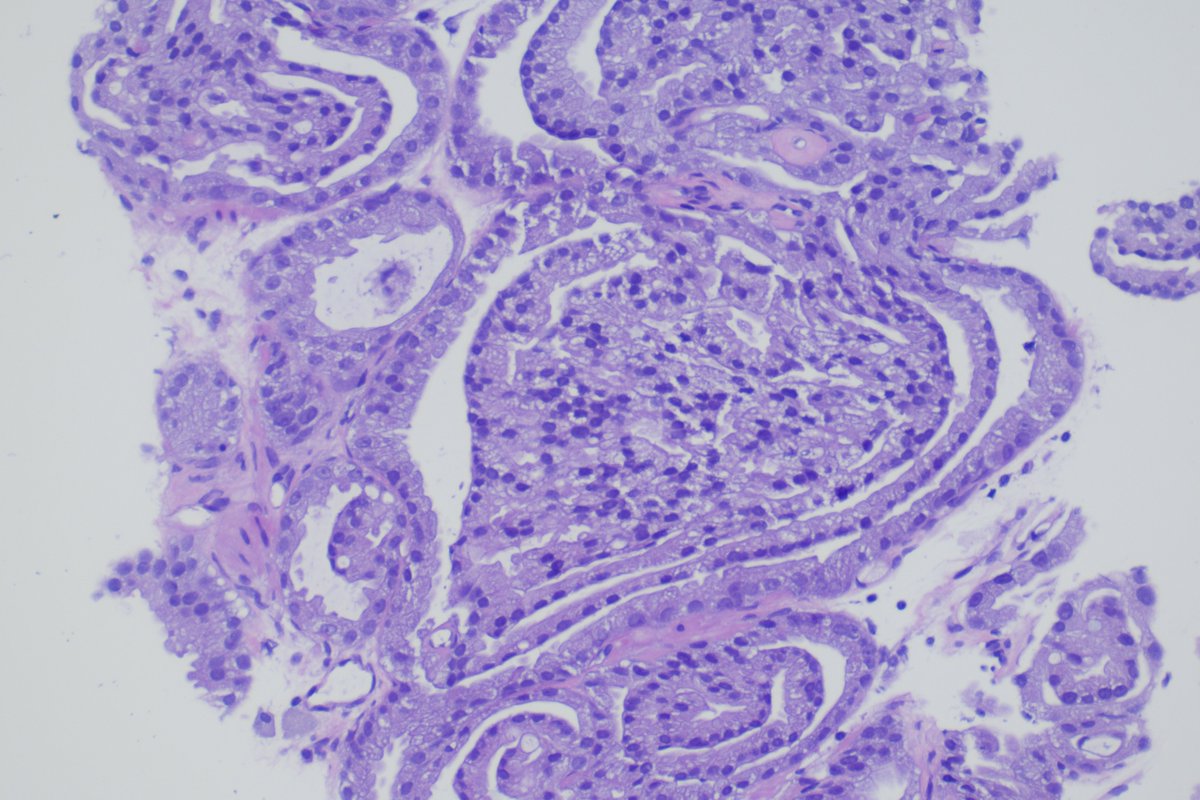

Interested in spatial transcriptomics? Consider reading our pilot study on spatial profiling of glomeruli in pauci-immune focal necrotizing glomerulonephritis!

kidney360.asnjournals.org/content/early/…

Pauci-immune focal necrotizing glomerulonephritis entails heterogeneous glomerular lesions. This study shows benefits of spatial profiling heterogeneous glomerular injury characterization, indicating molecular correlates of glomerular injury in piFNGN bit.ly/KID0004612022